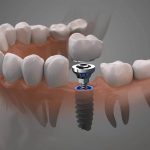

Dentist That Do Implants Near Me

Visiting a dentist that do implants near me requires an adequate preparation so that you will be able to get the best result. Call our Dental implants dentist in Houston.

Visiting a dentist that do implants near me requires an adequate preparation so that you will be able to get the best result. Call our Dental implants dentist in Houston.